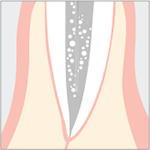

Perio (Sulama ve Temizleme)

Resimler SHINMONJI IMPLANT CENTER tarafından sağlanmıştır

Kanal tedavisi temizliği

Bozuk dosyaların kaldırılması